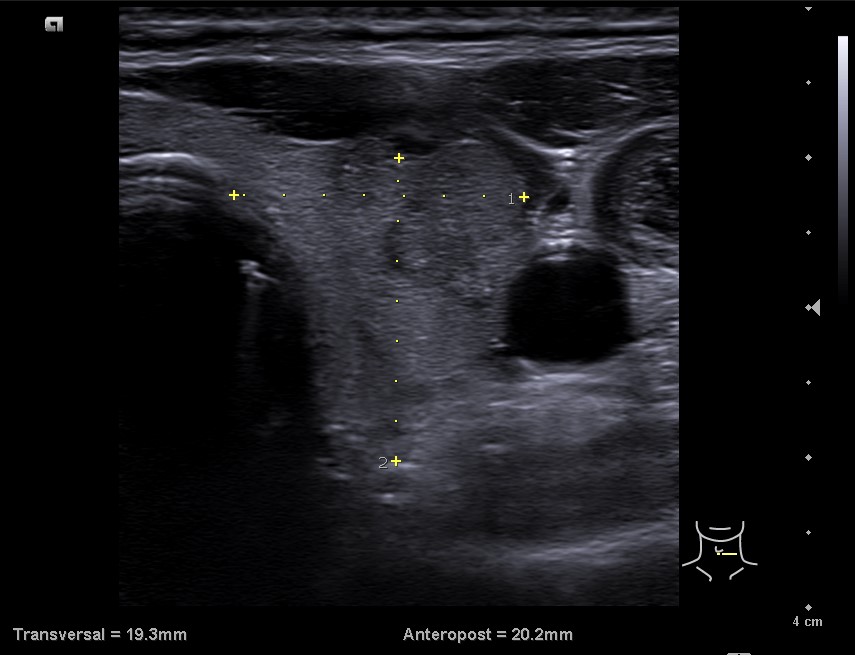

En la ecografía tiroidea se observa en LTI nódulo de 10 mm de bordes mal definidos, lobulado, mayormente sólido, más alto que ancho, isoecogénico, halo periférico hipoecoico, vascularización difusa, que sugiere TIRADS 5. Ausencia de flujo en Vena yugular interna izquierda, ensanchada, que sugiere trombosis yugular aguda o subaguda y junto a ella, posible conglomerado adenopático.